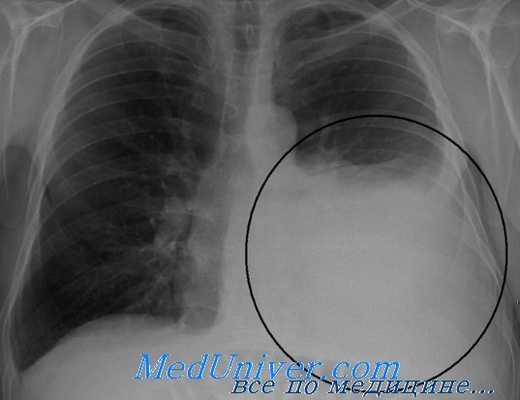

Рентгенограмма при гемотораксе

Важно выполнить рентгенографию грудной клетки сразу же после установки трубки. Это поможет подтвердить ее правильное расположение и оценить полноценность эвакуации жидкости и воздуха из плевральной полости. При подозрении на остаток внутриплевральной жидкости следует ввести вторую дренажную трубку. Неспособность полностью эвакуировать кровь из плевральной полости является одним из показаний для раннего хирургического вмешательства при повреждениях груди. Полная эвакуация воздуха и крови из плевральной полости важна для полноценного расширения легкого. Это поможет уменьшить кровотечение и утечку воздуха из легкого, а также снизит риск последующей эмпиемы.